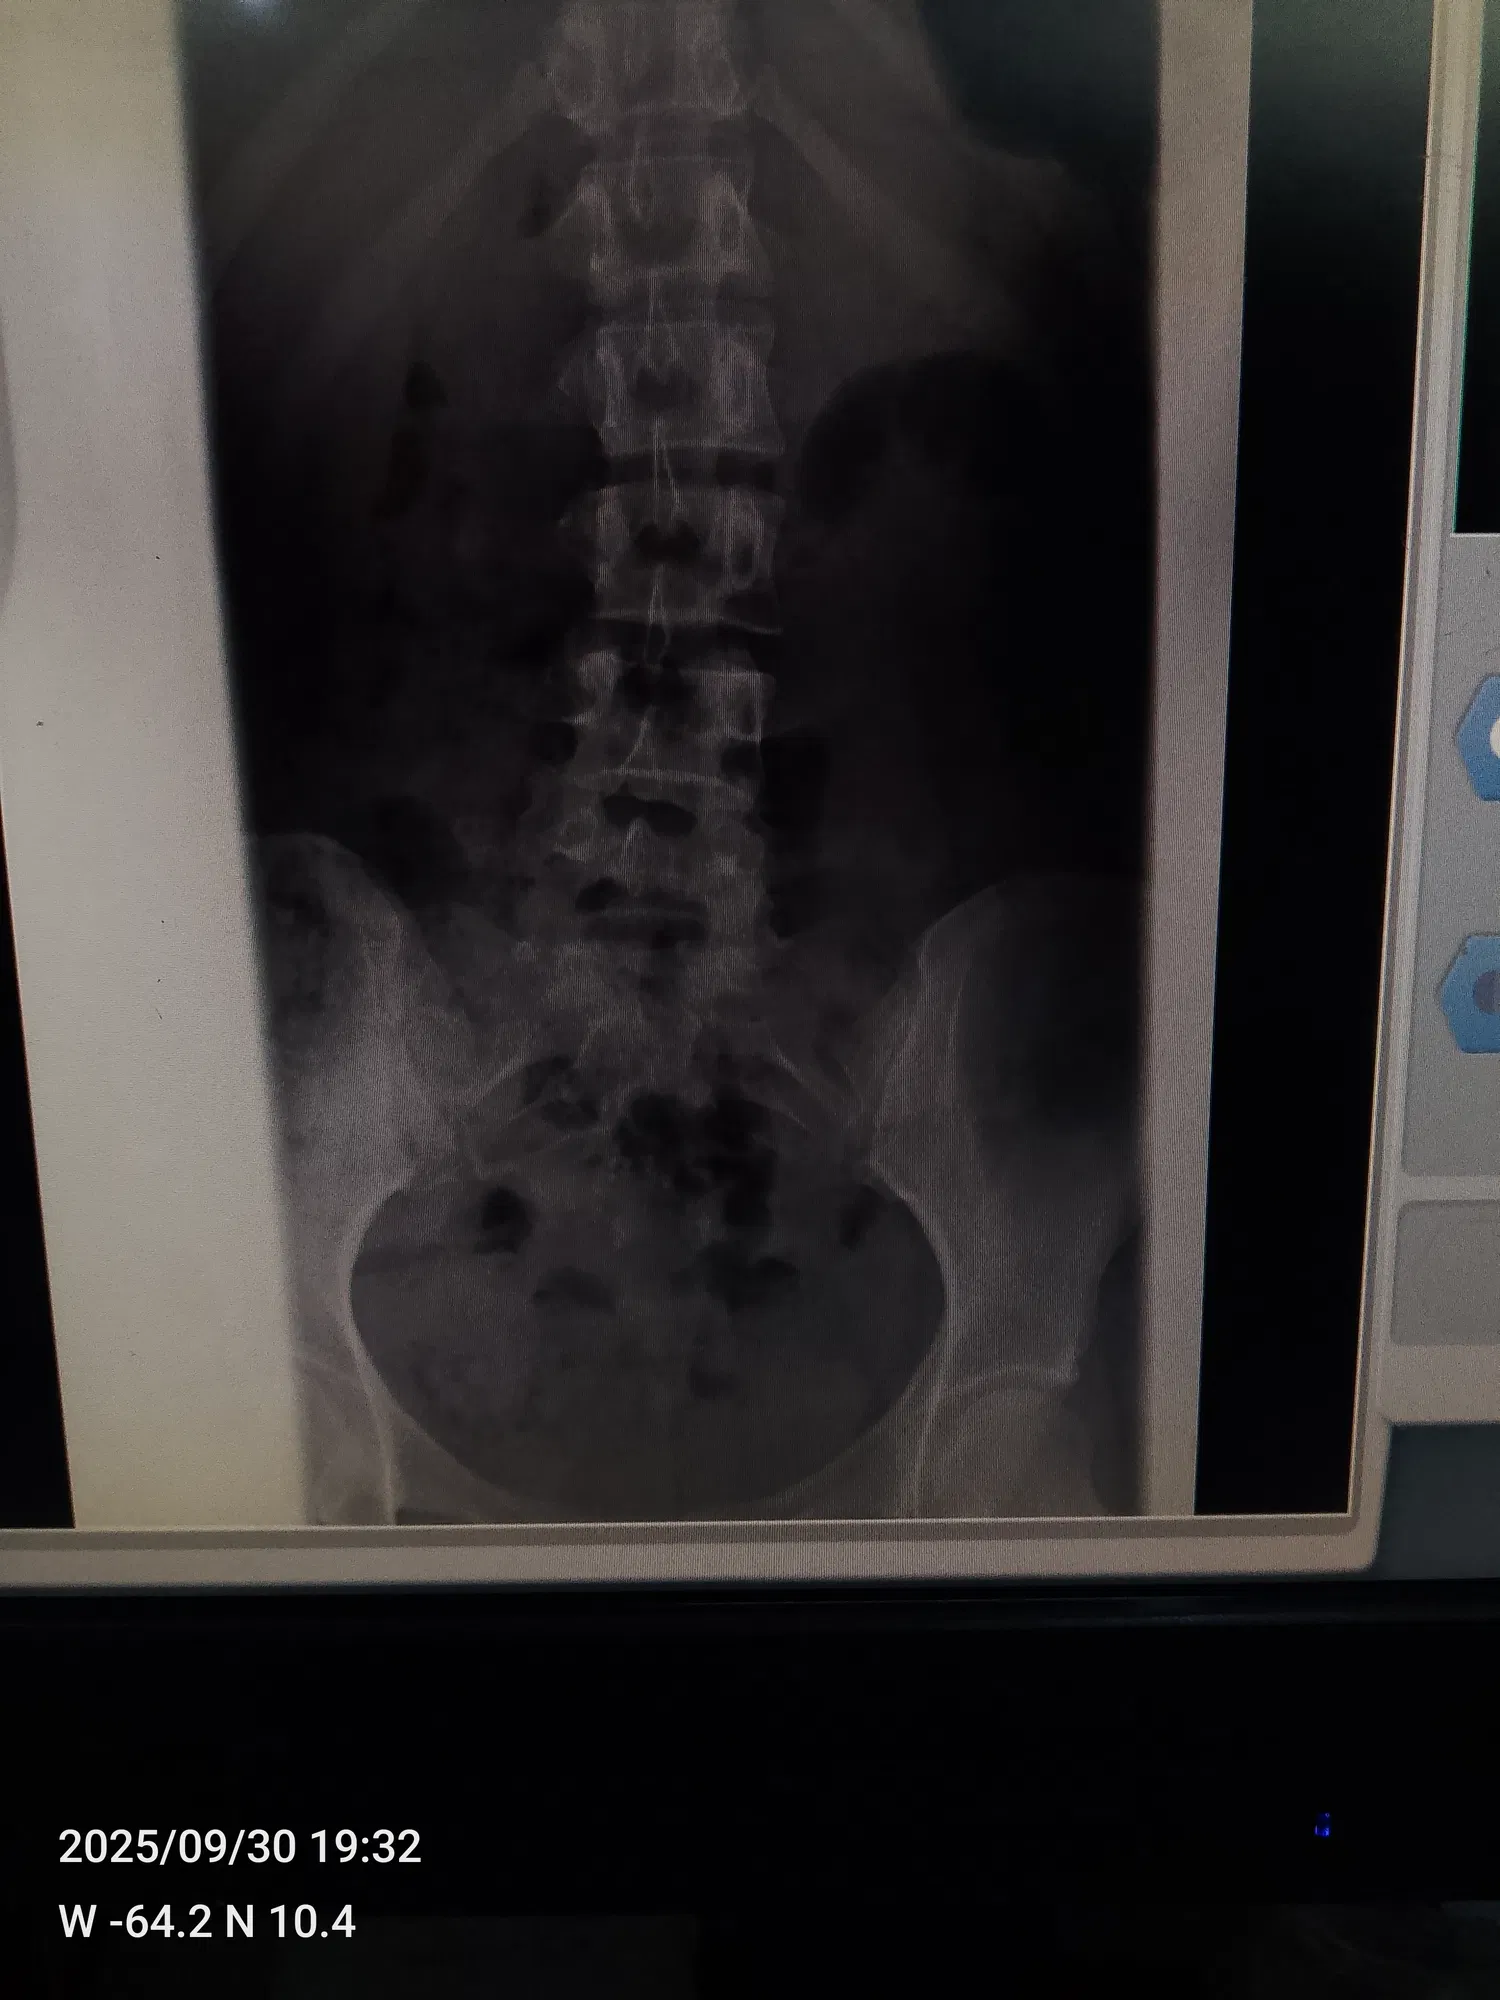

<liketuimages> <center>         </center> </liketuimages> ### Holaaa queridos amigos,¿cómo han estado? espero que hayan tenido un excelente fin de semana ❤️✨ he estado un poco perdida de por acá ya que me he estado sintiendo demasiado mal 😣 hace días les comenté que fui al traumatólogo ya que me había caido en dónde trabajo y me di un golpe súper fuerte en la columna ☹️ >Hello dear friends, how have you been? I hope you had a great weekend ❤️✨ I've been a little absent from here because I've been feeling really bad 😣 A few days ago, I told you that I went to the orthopedist because I fell at work and hit my spine really hard ☹️ ---- ### Desde que me caí no aguanto los dolores en la columna, coxis y cervical, del mismo golpe que me di tuve un derrame ( parecía el periodo pero eso no era ya que yo ya había visto periodo ese mes) mi mamá me llevo a el traumatólogo y la doctora me mando un tratamiento y reposo por una semana,en las placas que me hice antes de ir no salía nada malo.. >Since I fell, I can't stand the pain in my spine, tailbone, and neck. From the same blow, I had a hemorrhage (it looked like my period, but it wasn't because I had already had my period that month). My mom took me to the orthopedist, and the doctor prescribed treatment and rest for a week. The X-rays I had taken before going didn't show anything wrong. --- ### Cumplí mi reposo y me tomé el tratamiento que me mandó la doctora pero la verdad eso no me hizo efecto me sentía muy mal, las pastillas me calmaban el dolor un poco ya después el dolor volvió más fuerte ☹️ fui y me hice otras placas más y el radiólogo nos dijo que estaba teniendo una pequeña desviación y que se veía como una fisura que fuera a el traumatólogo a ver que era, mi mamá me llevo nuevamente para que la doctora y la misma dijo que no tenía nada y me mandó a tomar pregabalina y la verdad amigos me tomé una sola pastilla y me dió taquicardia sentía que me iba a morir me dió mucho miedo y no me la tomé más, mi mamá tuvo que buscarme la cita con otro traumatólogo, así que el día martes el doctor Luis Cova me va a ver.. >I rested and took the treatment prescribed by the doctor, but honestly, it didn't work. I felt terrible. The pills calmed the pain a little, but then the pain came back even stronger. ☹️ I went and had more X-rays taken, and the radiologist told us that I had a slight deviation and that it looked like a crack. He said I should go to the orthopedist to see what it was. My mom took me back to the doctor, and she said there was nothing wrong and prescribed pregabalin. To be honest, friends, I took just one pill and it gave me tachycardia. I felt like I was going to die. I was really scared and didn't take any more. My mom had to make an appointment with another orthopedist, so on Tuesday, Dr. Luis Cova is going to see me. --- ### Muchas personas ya nos han dicho que si tengo una desviación y algo más que obviamente lo va a ver el doctor, así que bueno esperaré hasta el martes Pero les digo amigos, ese dolor me hace llorar es demasiado fuerte 😭☹️ por eso he estado perdida de por acá,ya pronto volveré con mucho contenido para ustedes ❤️ síganme en mis redes de tiktok e Instagram por allá siempre subo algo ❤️ mi usuario de tiktok es @Fiorem17 y de Instagram es @Fiorem19 >Many people have already told us that if I have a deviation and something else that the doctor will obviously see, then I'll wait until Tuesday. But I tell you, friends, that pain makes me cry, it's too strong 😭☹️. That's why I've been missing from here. I'll be back soon with lots of content for you ❤️ Follow me on TikTok and Instagram, I always post something there ❤️ My TikTok username is @Fiorem17 and my Instagram is @Fiorem19 --- ### Acá les dejare algunas fotos que me he tomado jajaja y les quiero mostrar una torta que hice hoy en la mañana con ayuda de mi hermano ajajaja la hice en mi cuarto sentada en la cama así que fue un rato hacerla jajajaja y quedó linda, les dejare también las fotos de las placas por si algunos de ustedes es doctor las vea y me dice si ve algo malo por fa ☹️☹️☹️ >Here are some photos I took, hahaha, and I want to show you a cake I made this morning with my brother's help, hahaha. I made it in my room sitting on my bed, so it took a while, hahaha, but it turned out cute. I'll also leave you the photos of the X-rays in case any of you are doctors and can take a look and tell me if you see anything wrong, please ☹️☹️☹️ --- ##### <div class="pull-left"> - ### El texto es completamente de mi autoría. </div> ##### <div class="pull-right"> - ### The text is entirely by me. </div> --- ##### <div class="pull-left"> - ### Traducción realizada con DeepL Traslate. </div> ##### <div class="pull-right"> - ### Translation using DeepL Traslate. </div> --- For the best experience view this post on [Liketu](https://liketu.com/@fiorem17/un-nuevo-post-para-ustedes)